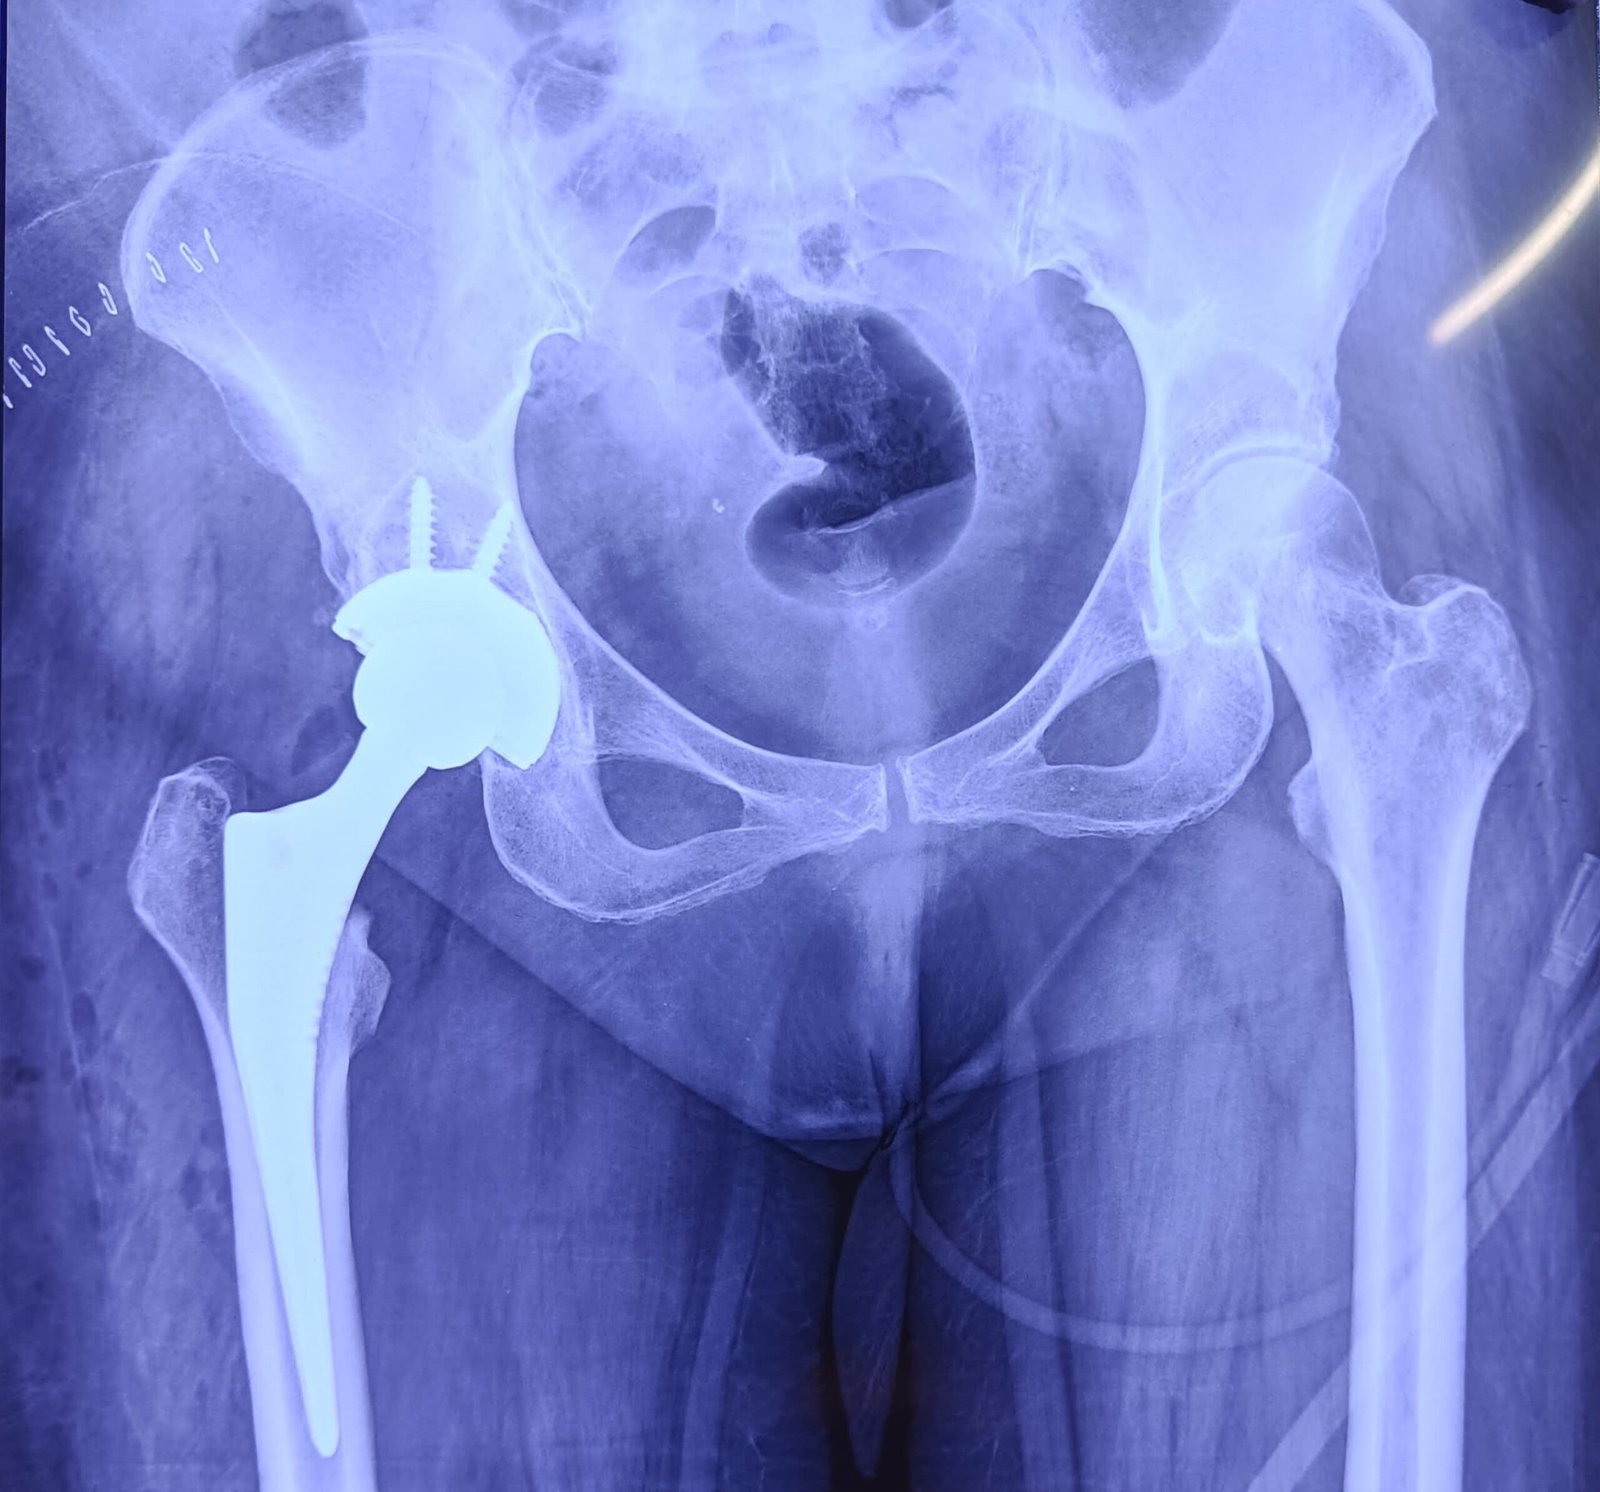

Post-Op X-Ray